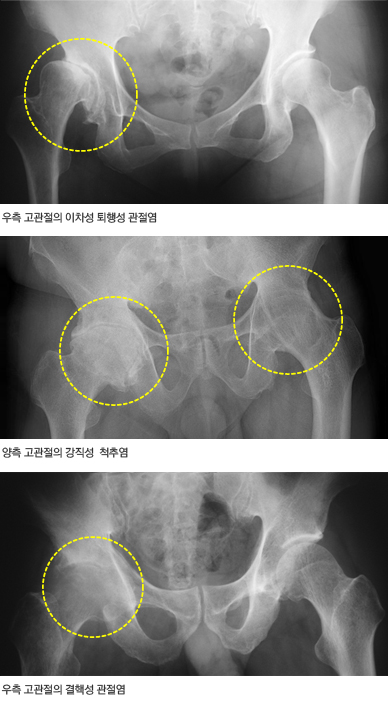

고관절에도 다른 관절과 마찬가지로 모든 종류의 관절염이 발생할 수 있다. 1) 퇴행성 고관절염: 가장 흔한 형태의 관절염으로서 특별한 원인 없이 나이가 들면서 관절이 나빠지는 일차성 퇴행성 고관절염과 선천성 및 후천성 질환 또는 외상으로 관절이 변형되거나 손상된 후 관절이 나빠지는 이차성 퇴행성 고관절염이 모두 발생할 수 있다. 동양인의 경우 대부분 이차성이며 일차성은 드물다. 그 이유는 확실치 않으나 아마도 서양인이 체격이 커서 고관절에 체중 부하가 많이 되기 때문인 것으로 해석되고 있다. 2) 류마티스 계통 고관절염: 류마티스 관절염을 비롯한 모든 류마티스 계통의 관절염이 고관절에 생길 수 있는데 이들 중에서 강직성 척추염에 의한 고관절염은 비교적 흔하다. 3) 감염성 고관절염: 최근에는 그 빈도가 많이 줄었으나, 일반 세균에 의한 화농성 고관절염이나 결핵균에 의한 결핵성 고관절염이 발생한다. 화농성 고관절염은 관절 파괴 속도가 빠른데, 급성의 경우 고열과 함께 심한 통증이 있으며 응급 수술을 필요로 하는 경우가 많다. 골관절 결핵 중 결핵성 고관절염은 척추 결핵 다음으로 자주 발생한다. 4) 특수 고관절염: 색소 융모 결절성 활액막염, 통풍성 고관절염, 신경병성 고관절염 등도 발생할 수 있으며, 조직 검사로도 분류가 불가능한 비특이적 고관절염도 있다. 5) 일과성 고관절 활액막염: 소아기에 주로 발생하는 비특이적 염증성 질환으로 10세 이하 소아에서 고관절 통증의 가장 흔한 원인이지만 성인에서도 발생할 수 있다. 특별한 치료를 하지 않아도 후유증 없이 저절로 치유된다. 초기에 감염성 고관절염이나 류마티스 고관절염 혹은 소아기 대퇴골두 무혈성 괴사증인 레그-깔베-퍼테스(Legg-Calve-Perthes) 병과 구별하는 것이 중요하다.

고관절염 X선 영상